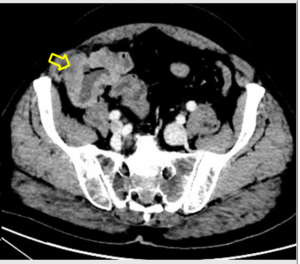

HALLAZGOS RADIOLÓGICOS